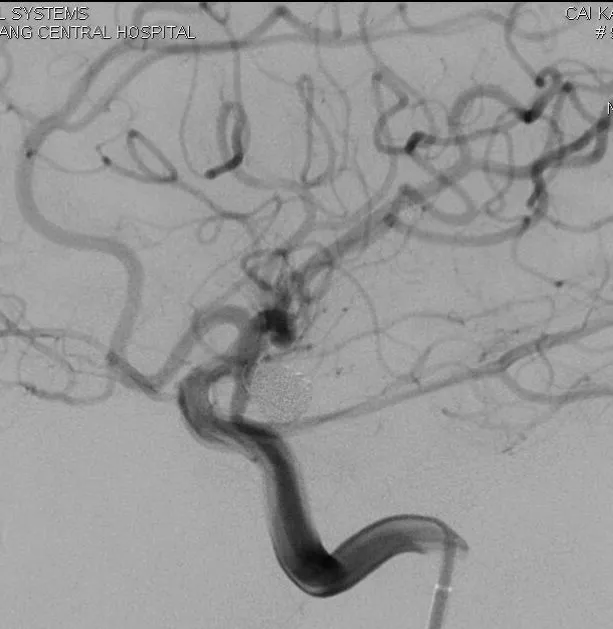

女,73岁,蛛网膜下腔出血量还挺多的,H-H 分级4级

造影显示左侧后交通动脉瘤

椎动脉造影没发现大脑后动脉,双侧的大脑后动脉都是由颈内动脉-后交通动脉发出,双侧胚胎型大脑后动脉